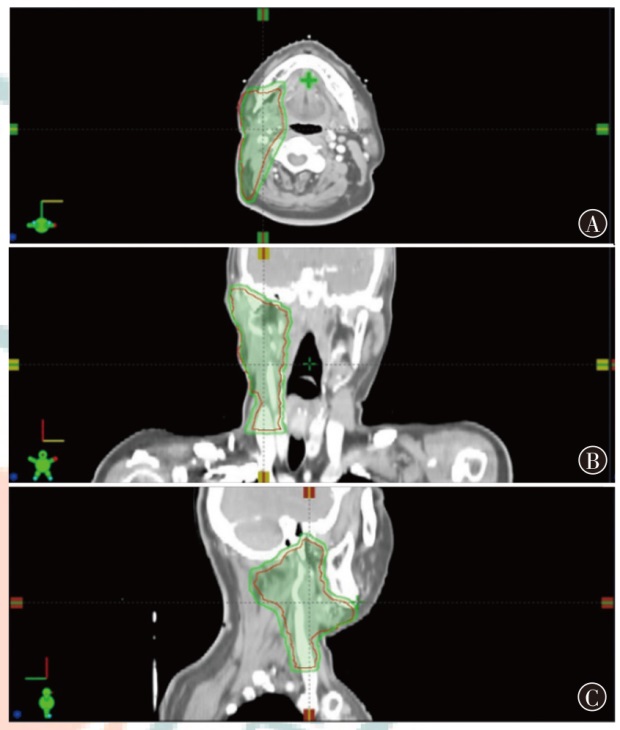

目的探索质子调强放疗(IMPT)和光子容积弧形调强放疗(VMAT)应用于典型头颈部恶性肿瘤的剂量学特点。方法以2023年12月至2024年12月山东省肿瘤防治研究院(山东省肿瘤医院)收治的鼻咽癌、腮腺癌和喉癌患者各1例为研究对象,分别根据靶区和危及器官限值的临床处方要求制定IMPT和VMAT计划。评估3例患者两种计划的靶区适形指数(CI)、均匀性指数(HI)和梯度指数(GI),并评估危及器官的剂量学指标。结果鼻咽癌、腮腺癌和喉癌患者IMPT计划的CI分别为0.70、0.72和0.67,HI分别为0.11、0.08和0.08,GI分别为3.08、2.49和3.75;VMAT计划的CI分别为0.77、0.82和0.91,HI分别为0.12、0.10和0.04,GI分别为3.67、2.63和3.45。IMPT计划的CI略低于VMAT计划,IMPT计划的HI与VMAT计划相当,鼻咽癌和腮腺癌患者IMPT计划的GI低于VMAT计划,喉癌患者IMPT计划的GI高于VMAT计划,且均在临床接受范围。IMPT计划在鼻咽癌、腮腺癌和喉癌治疗中表现出显著的剂量优势:对于鼻咽癌患者,IMPT计划的左、右晶体Dmax比VMAT分别降低了54.1%和50.4%,口腔和喉头的Dmean分别降低了40.5%和49.6%。对于腮腺癌患者,IMPT的脑干和脊髓Dmax比VMAT分别降低了66.2%和40.5%。对于喉癌患者,IMPT的脊髓Dmax比VMAT降低了77.0%,而甲状软骨Dmean比VMAT增加了8.0%。对于患者体内的额外剂量,以患者体内10%、30%和50%的处方剂量区域所占的绝对体积为例,鼻咽癌患者IMPT比VMAT计划分别降低了29.7%、29.6%和34.9%,腮腺癌患者IMPT比VMAT计划分别降低了61.0%、39.7%和17.4%,喉癌患者IMPT比VMAT计划分别降低了63.9%、31.7%和4.1%。结论相比VMAT计划,IMPT计划可有效降低头颈部肿瘤靶区附近大部分危及器官的受照射剂量,但对于紧邻靶区的串型器官,其剂量可能更高,需要引起关注。

ObjectiveTo investigate the dosimetric characteristics of intensity modulated proton therapy (IMPT) and photon volumetric modulated arc therapy (VMAT) in typical head and neck malignant tumors.MethodsThree types of typical head and neck tumors (nasopharyngeal carcinoma, parotid gland carcinoma, laryngeal carcinoma) treated at Shandong Cancer Hospital and Institute from December 2023 to December 2024 were taken as research subjects. IMPT and VMAT radiotherapy plans were created according to clinical prescription requirements of target and organs at risk limits respectively. The conformity index (CI), homogeneity index (HI) and gradient index (GI) for target coverage of two radiotherapy plans were evaluated for 3 patients, as well as the dosimetric indicators of organs at risk.ResultsThe CI of IMPT for nasopharyngeal carcinoma, parotid gland carcinoma and laryngeal carcinoma were 0.70, 0.72 and 0.67, respectively. The HI were 0.11, 0.08 and 0.08, respectively. The GI were 3.08, 2.49 and 3.75, respectively. The CI of VMAT plans were 0.77, 0.82 and 0.91, respectively. The HI were 0.12, 0.10 and 0.04, respectively. The GI were 3.67, 2.63 and 3.45, respectively. The results showed that CI of IMPT plan was slightly lower than that of VMAT plan, and HI of IMPT plan was comparable to that of VMAT plan, the GI of the IMPT plan for patients with nasopharyngeal carcinoma and parotid gland carcinoma was lower than that of the VMAT plan, and the GI of the IMPT plan for patient with laryngeal carcinoma was higher than that of the VMAT plan, and all were within the clinically acceptable range. The IMPT plan has demonstrated significant dose advantages in the treatment of nasopharyngeal carcinoma, parotid gland carcinoma and laryngeal carcinoma. For patient with nasopharyngeal carcinoma, the IMPT plan reduced the Dmaxof the left and right crystals by 54.1% and 50.4%, respectively, compared to VMAT plan, and reduced the Dmeanof the oral and laryngeal tissues by 40.5% and 49.6%, respectively. For patient with parotid gland carcinoma, IMPT plan reduced the Dmaxof the brainstem and spinal cord by 66.2% and 40.5%, respectively, compared to VMAT plan. For patient with laryngeal carcinoma, IMPT reduced spinal cord Dmaxby 77.0%, while thyroid cartilage Dmeanincreased by 8.0% compared to VMAT plan. For the additional dose in the patients' body, taking the absolute volumes occupied by the prescribed dose areas of 10%, 30%, and 50% in the patients' body as examples, IMPT plan of nasopharyngeal carcinoma patient decreased by 29.7%, 29.6%, and 34.9% compared to VMAT plan, respectively. IMPT plan of parotid gland carcinoma patient decreased by 61.0%, 39.7%, and 17.4% compared to VMAT plan, respectively. IMPT plan of laryngeal carcinoma patient decreased by 63.9%, 31.7%, and 4.1% compared to VMAT plan, respectively.ConclusionsCompared with VMAT plan, IMPT plan can effectively reduce the irradiation dose of most organs at risk near the target of head and neck tumors, but the dose of string organs close to the target area may be higher, which needs attention.